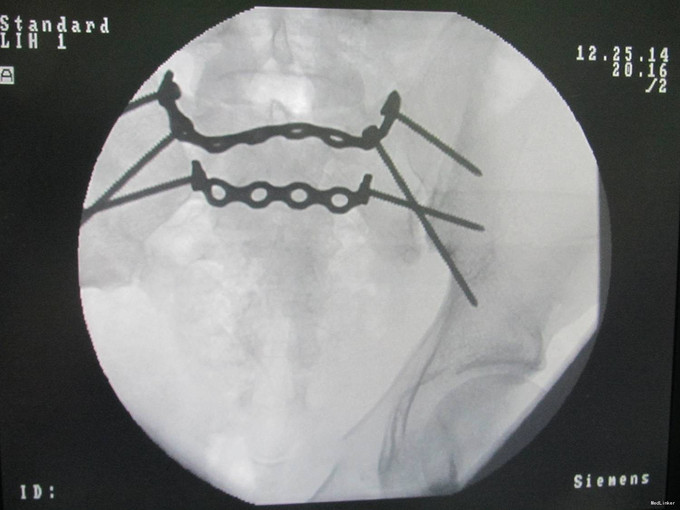

患者于2014年12月19日下午被车挤伤,右髋部及腰部疼痛肿胀,髋关节活动受限,急诊送至当地医院,给予补液输血对症治疗,输血量不详,留置导尿,患者为进一步治疗,于2014年12月22日晚转入我院急诊后收入我科。

患者会阴区肿胀,阴囊肿胀,青紫,骨盆分离挤压试验(+),纵向叩击痛(+),右小腿外侧及足部感觉减退麻木,右踝关节背伸肌力1级,跖屈肌力3级,右踇趾背伸肌力1级,跖屈肌力3级,双侧足背动脉可触及搏动。

诊断:骨盆骨折(Tile C1 型),骶骨骨折(Denis 2型), 腰骶神经损伤 患者入院后完善检查,给予抗炎,补液等对症治疗后,全麻下行腰髂固定切口复位钢板内固定术,腰5神经根探查术,术后给予抗炎,消肿,冷敷,患肢抬高等对症治疗。观察患者双下肢感觉及神经运动情况。患者每天换药观察切口愈合情况,无红肿及渗出,待伤口14天后予以拆线治疗,予以出院,给予康复处方。